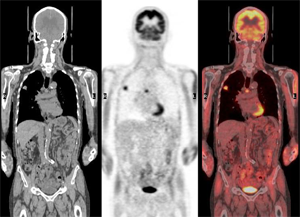

透析患者さんには腎がんの発生が多いというデータがあります。しかし、CTや超音波検査などでも、発見が困難なことが少なくありません。このプロジェクトは透析患者さんの腎がん早期発見を目的としてFDG-PETの有用性を調査するものです。

プロジェクトは現在進行中です。

透析患者さんでPET検査を受けてくださる方を募集しています。